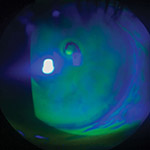

Central Serous Chorioretinopathy

A small break that forms in the pigment layer of the retina.